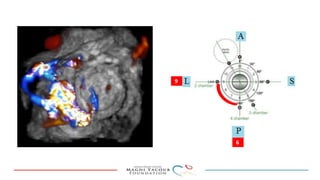

This document provides an overview of percutaneous prosthetic valve leakage (PVL) closure, including indications, approaches, techniques, and closure devices. It discusses that over 210,000 prosthetic valve surgeries are performed each year, with PVL occurring in some cases. While surgical closure has a high mortality rate, percutaneous closure has a procedural success rate of 86% and less complications. Indications for closure include symptomatic heart failure, hemolysis, rocking prosthesis, or leaks over 30% of the sewing ring. Techniques discussed include retrograde and transapical approaches using devices like the Amplatzer and Occlutech plugs. A team approach and techniques like sequential deployment are emphasized for